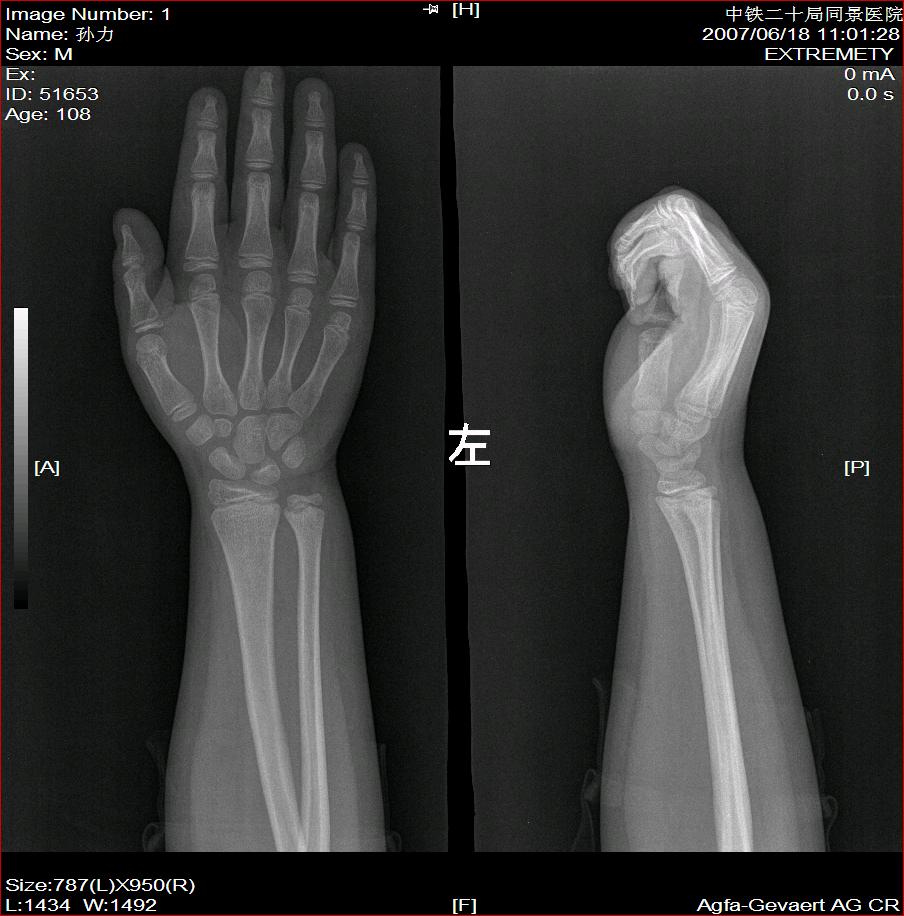

标题: X2504:M17Y,高中生,身高不足1.2米,智力正常 [打印本页]

年龄17岁,身材矮小(1.2m),全身骨骼发育迟缓,骨骺线仍较宽,但全身骨骼骨质正常,智力正常。

骨结构正常,骨骺线与17岁不符,豆状骨未见,相当7-8岁骨龄,结合智力正常,垂体性侏儒可能大。

考虑垂体侏儒的可能。依据1骨龄延迟,骨胳结构正常,智力正常。与甲状腺功能不足区别呆小症病人长骨及骨垢有改变,骨垢较正常小。椎体变扁。考虑垂体侏儒症。

骨结构正常,骨骺线与17岁不符,豆状骨未见,相当7-8岁骨龄,结合智力正常,支持垂体性侏儒症。

各部比例在正常范围,为均称型侏儒,可见于1、垂体性侏儒。2、致密性骨发育不全。3、turner氏综合症。本例骨密度正常,皮质边界清,显然不支持致密性骨发育不全,未见掌骨征阳性和指骨优势,turner氏综合症,可基本除外,剩下的只有垂体性侏儒了,建议垂体mri进一步检查,确定诊断。以上主要参考曹来宾教授发表的论文,侏儒症的临床x线分析

全身骨骼发育迟缓,骨骺线仍较宽与年龄不符。考虑垂体性侏儒可能大。